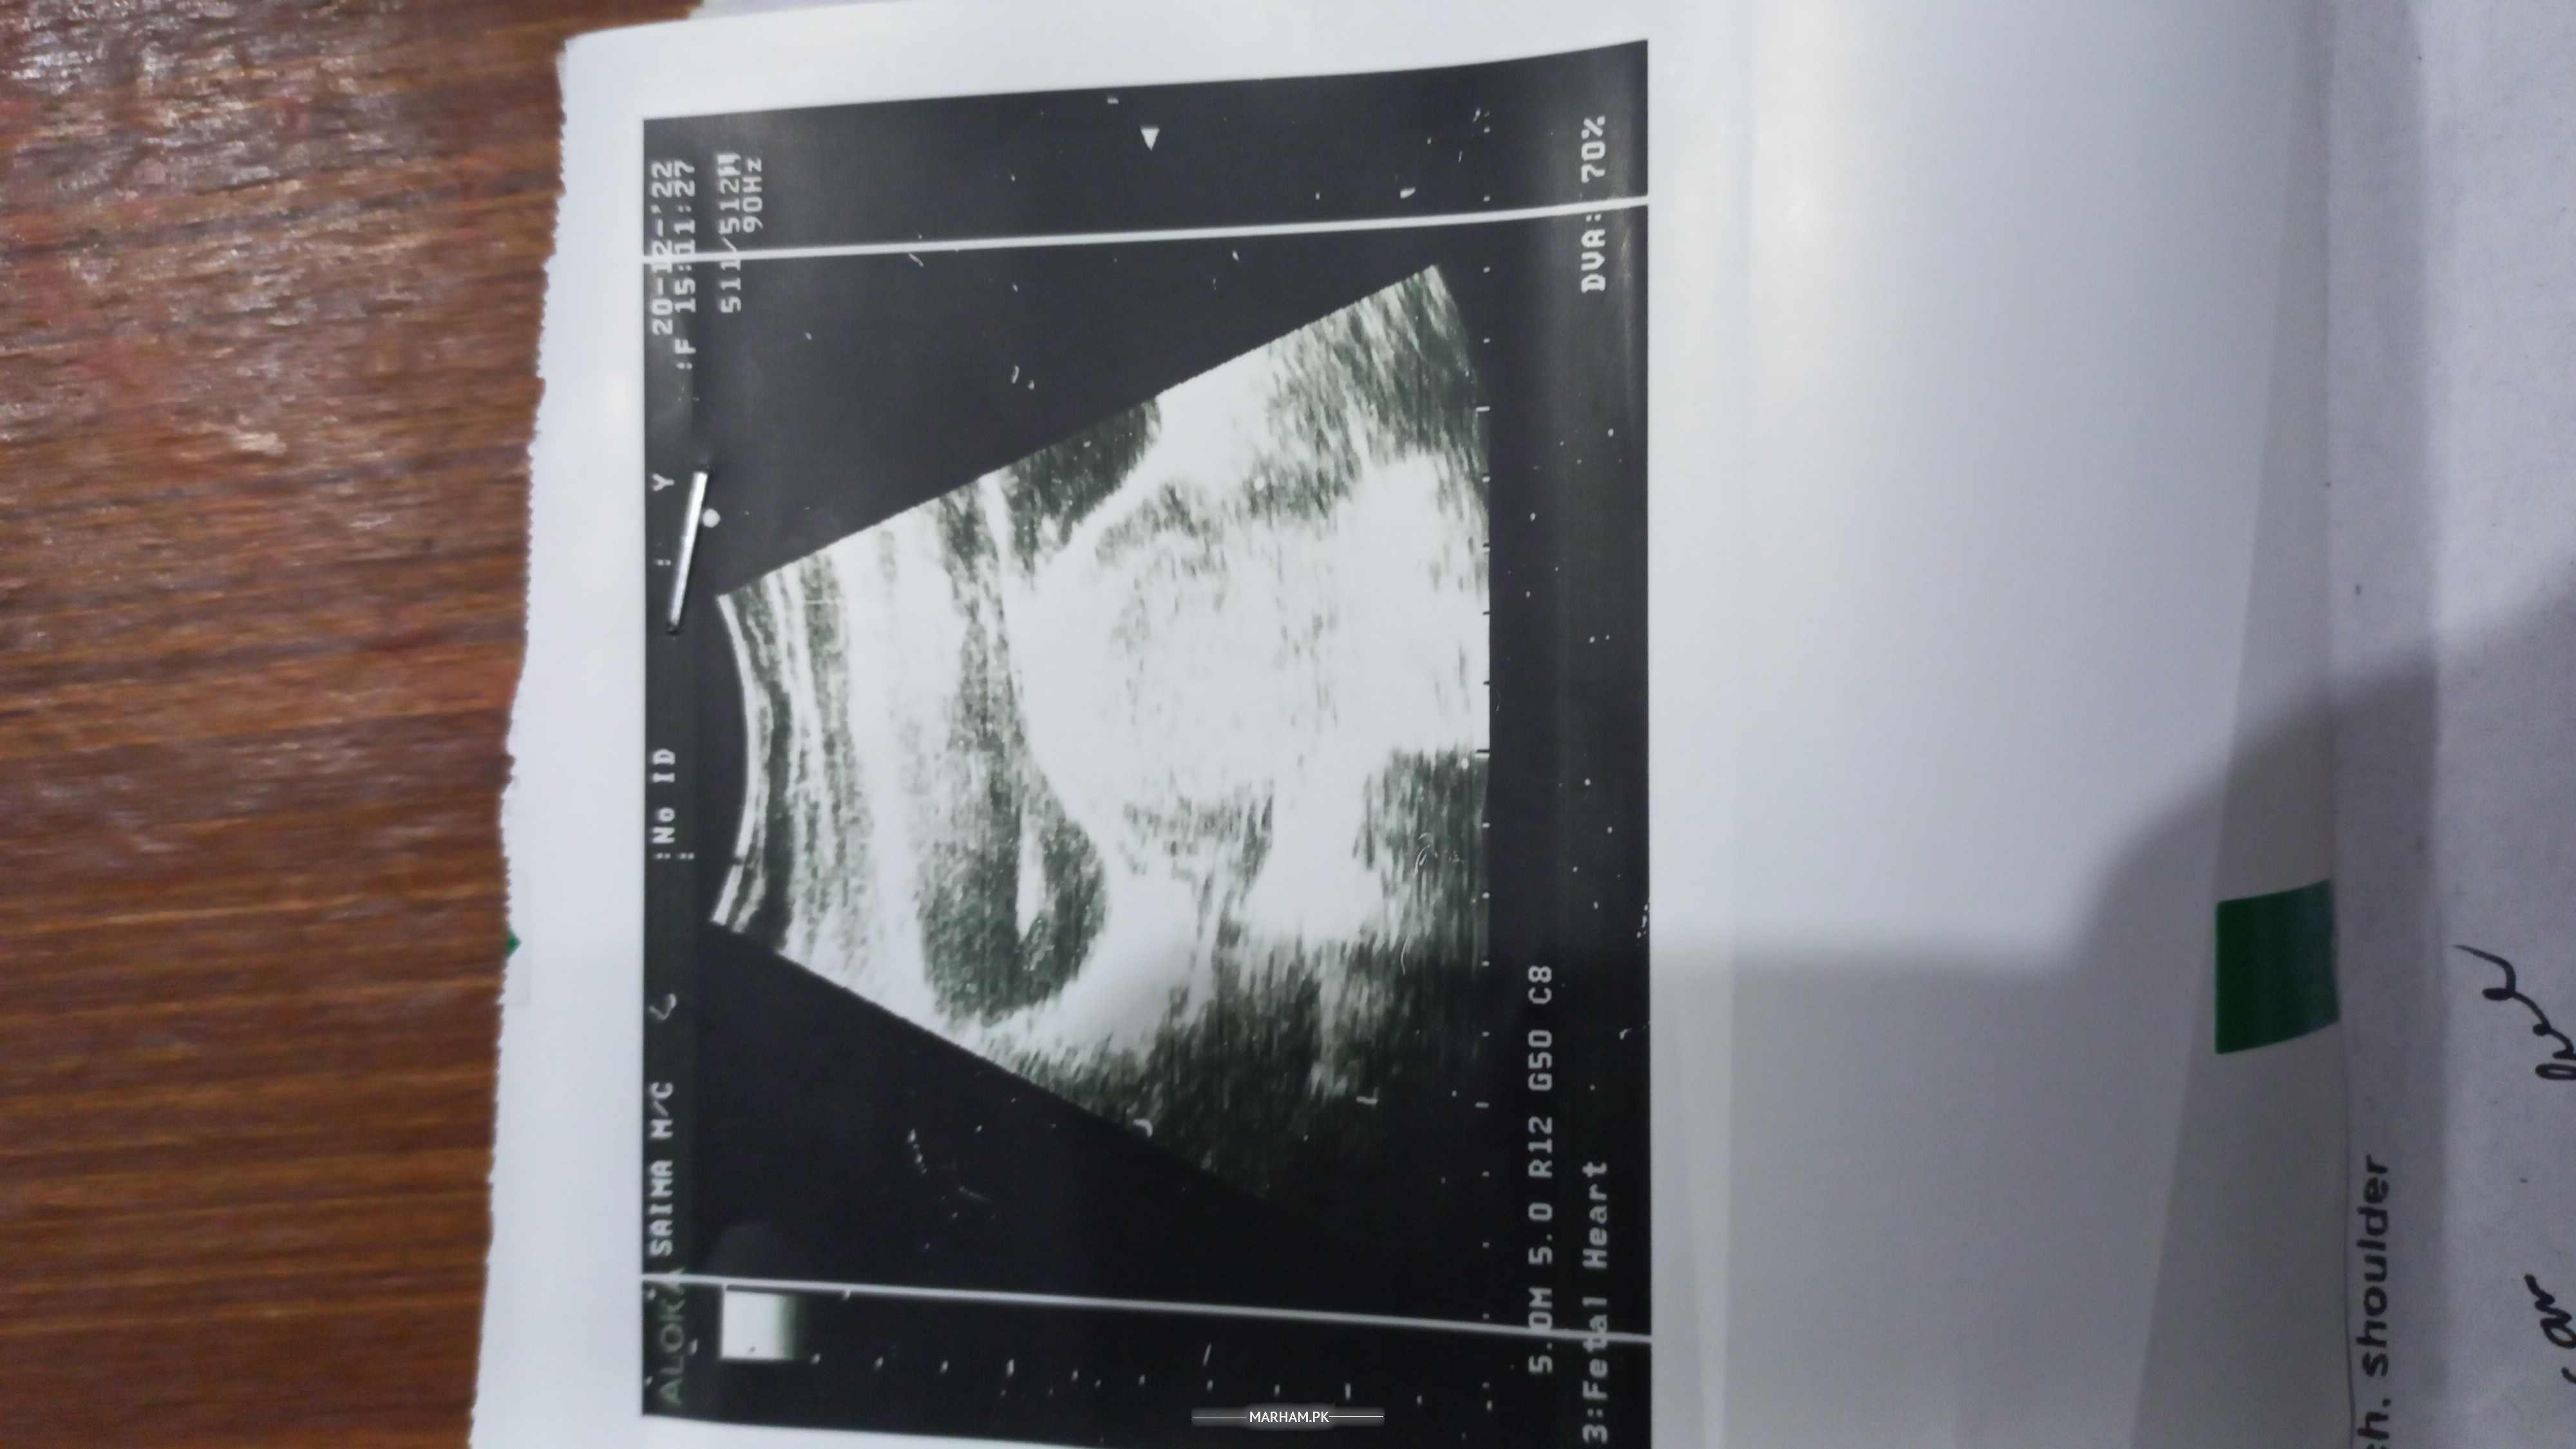

Asking for Self, Female, 26 years old, Lahore

I am married since march 2018.I already have miscarriages history. Now i am expecting i am sending you my Ultrasound scan Please tell me is this healthy or unhealthy Pregnancy

Its my ultrasound